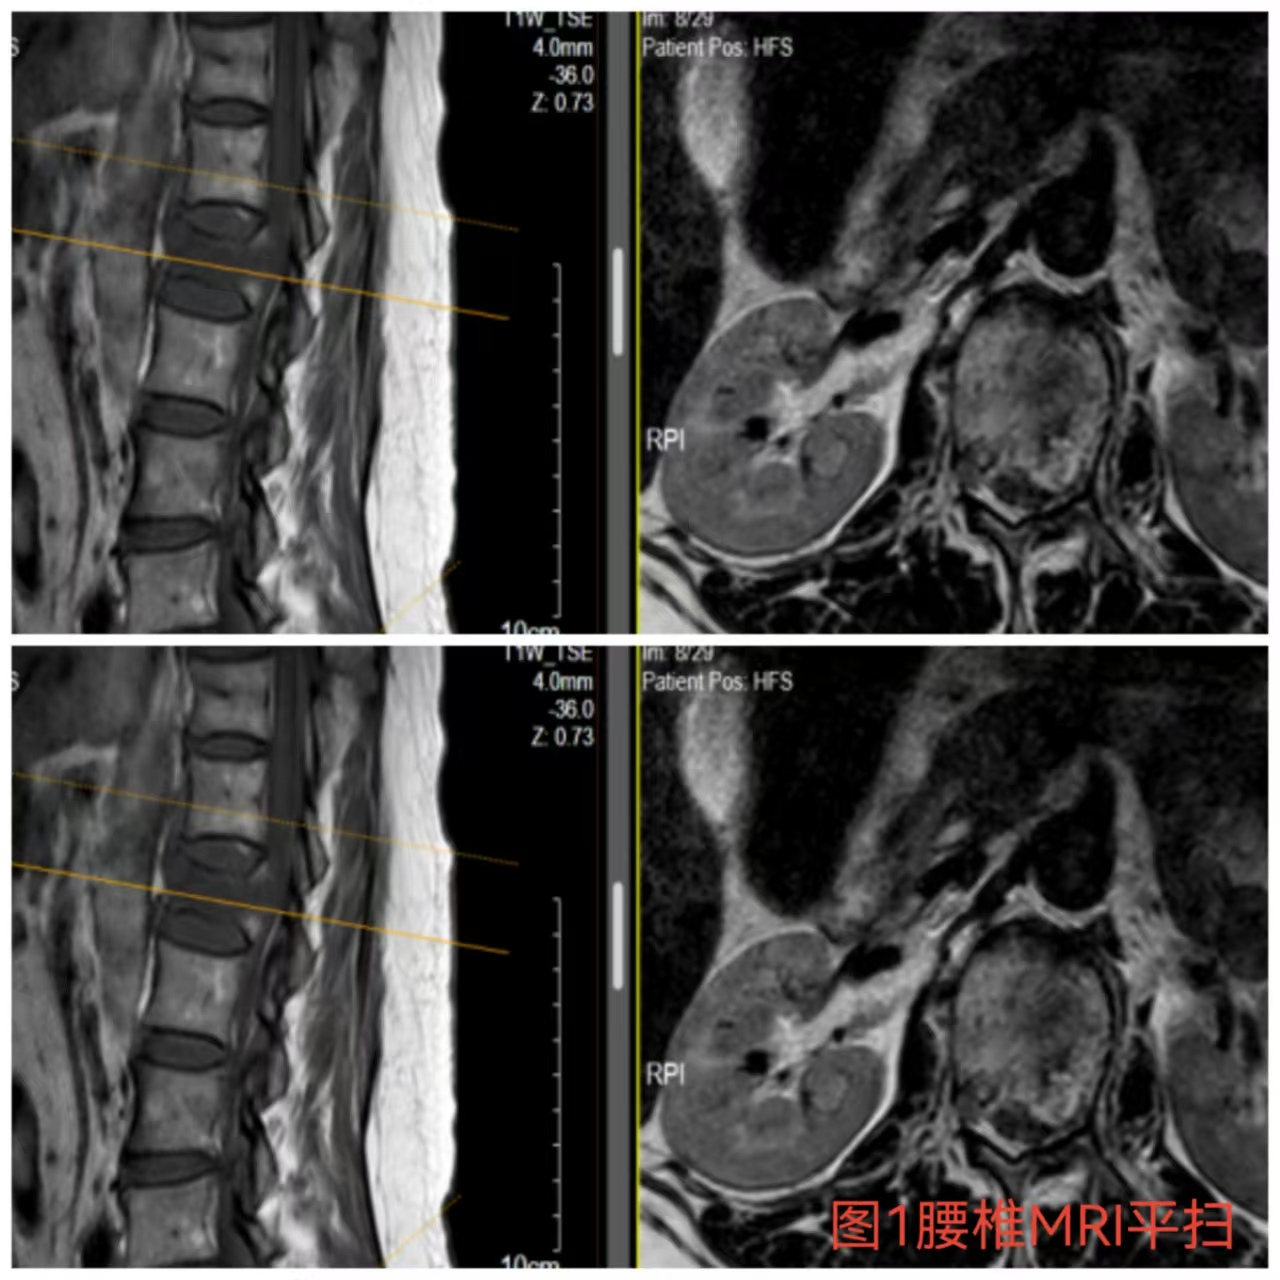

入院時患者躺在床上不能動彈,眼神中透漏著深深的無助,對于她來說這種傷情無疑是沉重的,尤其是腹股溝以下感覺消失、雙下肢肌力0級,這意味著其下肢無法活動及站立,仿佛被命運按下了暫停鍵;與病人及家屬充分溝通病情后,第一時間給予對癥治療,監測患者生命體征,行腰椎核磁檢查(圖1)提示:腰1椎體爆裂性骨折,椎體后緣塌陷致骨性椎管狹窄,壓迫脊髓神經,結合患者病情及輔助檢查可診斷為:“L1椎體爆裂性骨折伴雙下肢截癱”。

俞德亮副主任醫師深知病情的嚴重性,拖得時間越久,脊髓神經損傷癥狀越難以恢復,必須把握住早期減壓手術的關鍵時間窗,緊急帶領創傷骨科醫師團隊對該病情進行討論、制定手術方案,并成功為患者急診行“L1椎體爆裂性骨折伴截癱切開椎板切除+椎管探查減壓+骨折復位釘棒系統內固定術(圖2)”,該手術精確解除對脊髓神經的壓迫,并通過椎弓根螺釘內固定系統對受損的腰椎提供穩固的支撐,為后期的康復創造了良好的條件。